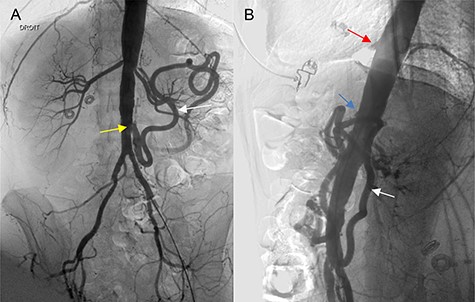

A 46-year-old woman presented with a history of abdominal angina, nausea and vomiting, and weighed 40.9 kg (body mass index 16.4). A computed tomographic angiography (CTA) was used as the imaging modality to evaluate the patient’s symptoms, which revealed occlusion of the celiac trunk (CT), superior mesenteric artery (SMA) and severe stenosis of the inferior mesenteric artery (IMA) at its origin. Mesenteric circulation was supplied via retrograde flow through the arc of the Riolan artery (Fig. 1A, B), with branches of the celiac artery patent at their origin. The two internal iliacs were patent, although both external iliacs were calcified. Coronary angiogram and cardiac echo were unremarkable. The patient underwent a repeated, extensive screening workup for hypercoagulable disorders and vasculitis, which turned out to be normal. The case was presented at a multidisciplinary meeting to evaluate revascularization options; we opted for an open reconstruction based on our experience, available literature reports, and the age and adequate cardiopulmonary reserve of the patient.

(A, B) Angiography of the abdominal aorta (preoperative), demonstrating the occlusion of the CT (red arrow) and SMA (blue arrow) with severe stenosis of the IMA (yellow arrow). Retrograde flow of the arc of the Riolan artery is shown (white arrow).